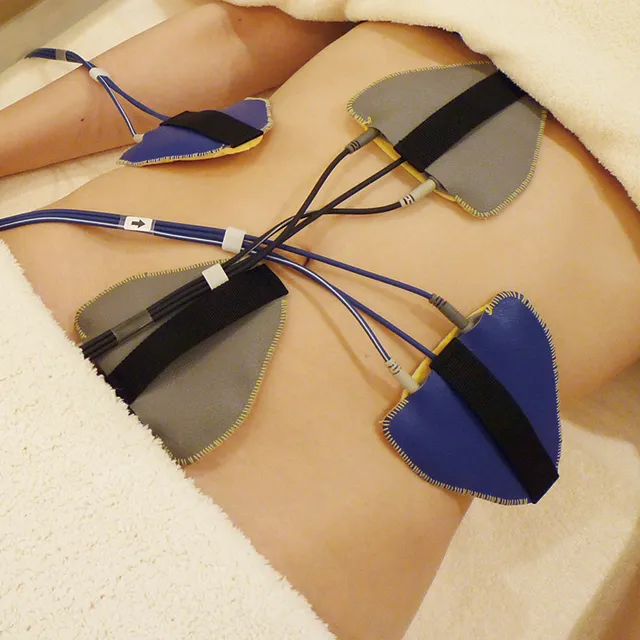

「マイナスの治療」と「プラスの治療」を効果的に組み合わせ、デザインしながら治療を行うことで、均整の取れた美しいボディラインが叶います。

医師の美的センスやデザイン力で効果が左右する脚痩せ、部分痩せ治療。筋肉、皮下組織、脂肪組織、骨格など、構造を知り尽くした院長の高見が生み出した独自の「タカミクリニック式メソッド」で、その方に適した治療を行います。

不必要な脂肪や発達しすぎた筋肉を改善する「マイナスの治療」

ダイエットでは細くならない筋肉質なふくらはぎを、脚痩せ注射で改善。